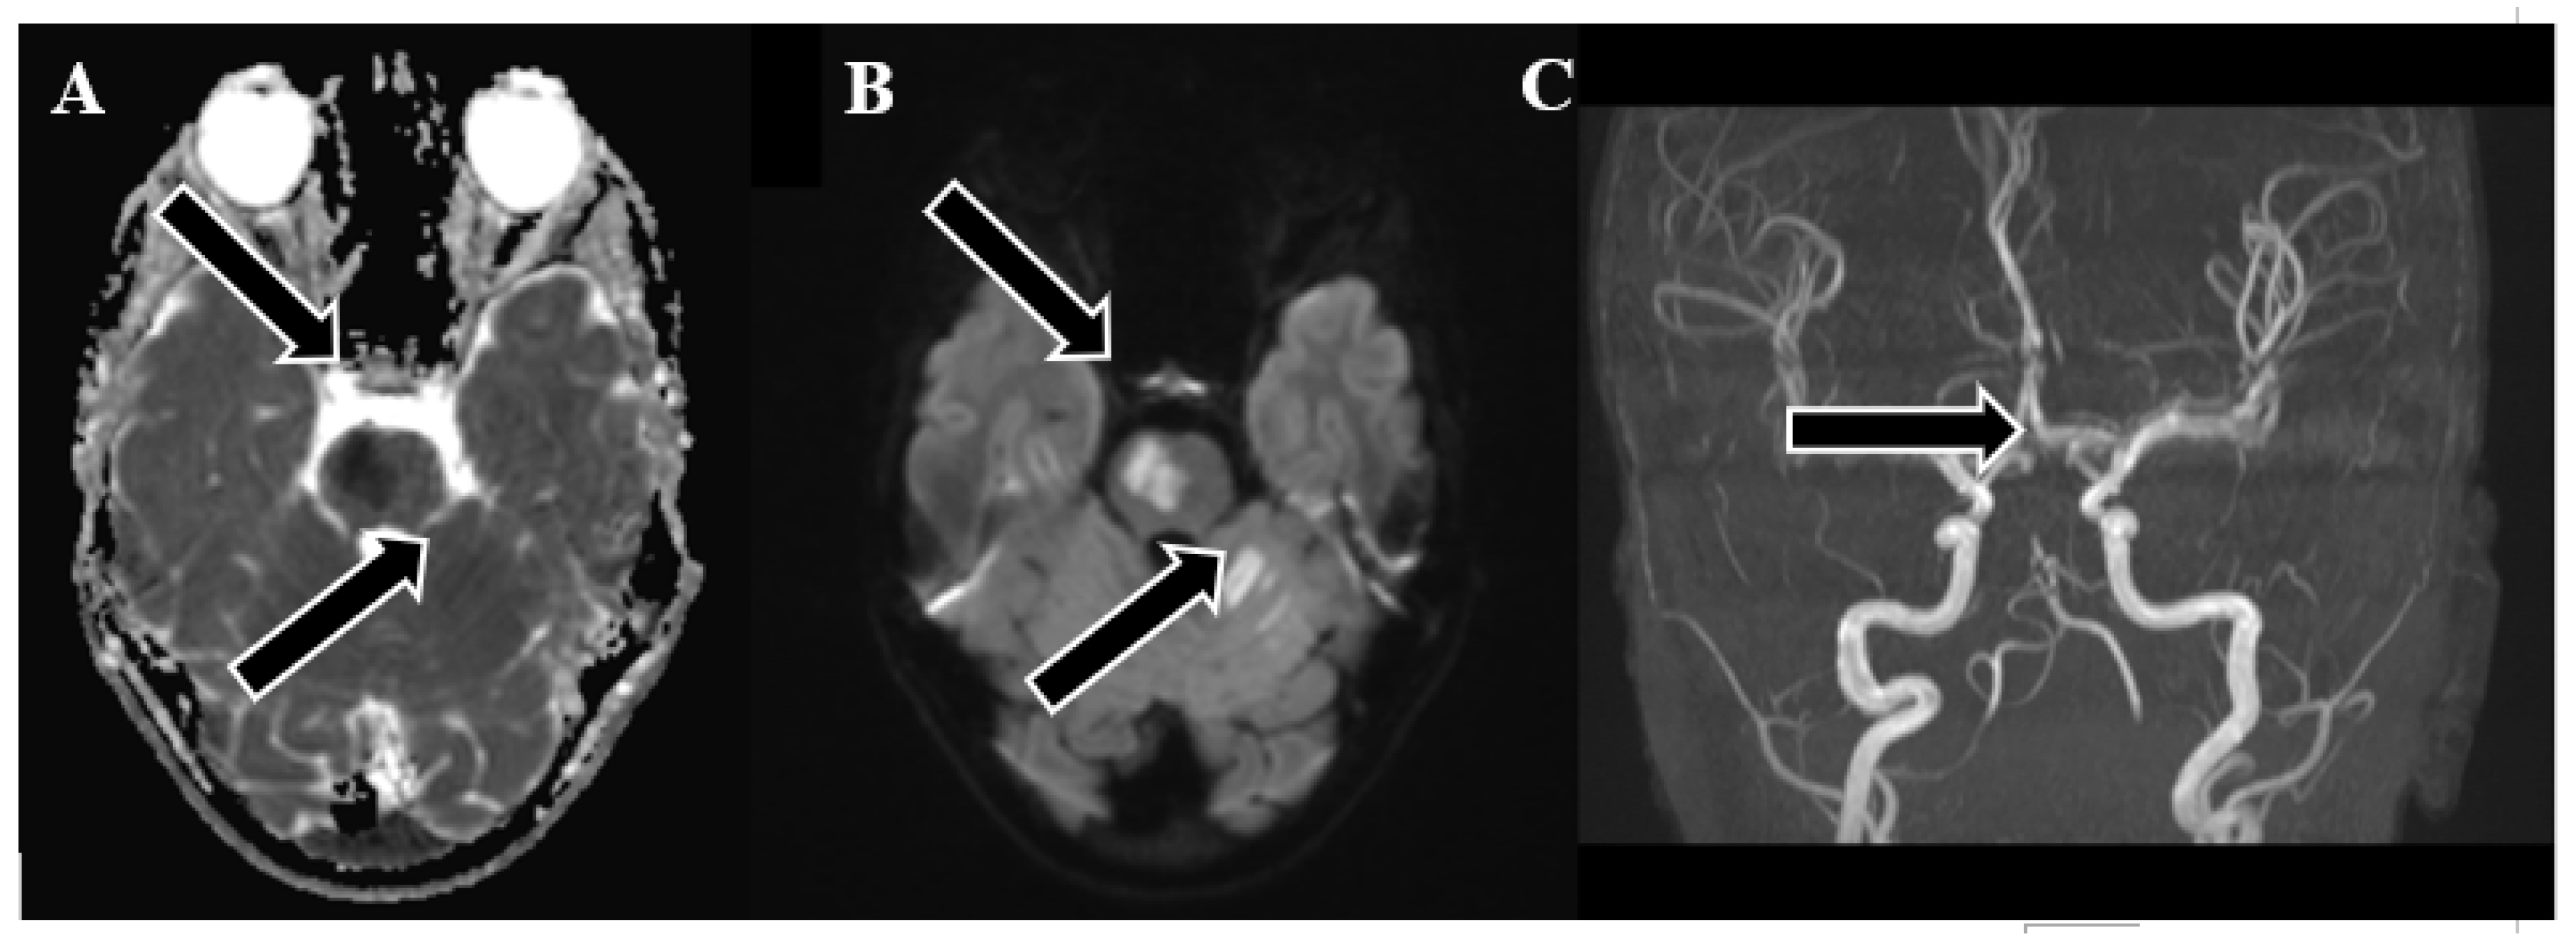

Figure 2. Emergency magnetic resonance imaging (MRI) before intervention. (A) Changes in the ADC map seen in the left PICA, as well as slightly in the AICA and SCA regions; (B) diffusion-weighted images showing acute changes in the left PICA, as well as slightly in the AICA and SCA regions; (C) MRA showing stop of flow in the distal 1/3 of the basilar artery.

Following 3.5 hours and in consultation with a pediatric specialist, the decision was made to transfer the patient to the Children's Clinical University Hospital for a more comprehensive diagnostic assessment. An emergency magnetic resonance imaging (MRI) was conducted, revealing acute ischemia within the vascularization area supplied by the left posterior inferior cerebellar artery (PICA). Moreover, this MRI also indicated involvement in regions supplied by the left anterior inferior cerebellar artery (AICA) and superior cerebellar artery (SCA). The magnetic resonance angiography (MRA) performed concurrently showed evidence of a thrombus causing occlusion in the distal one-third of the basilar artery (BA). This comprehensive imaging assessment illuminated the extent of the vascular compromise and provided critical information for further evaluation and treatment planning.